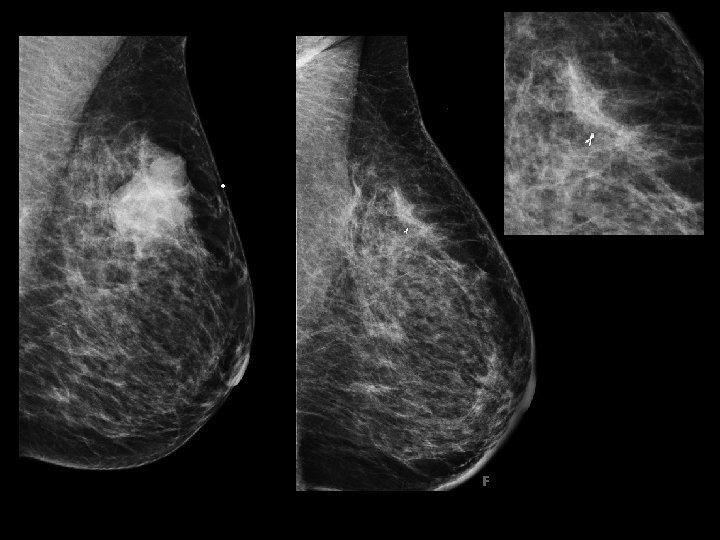

Proposed Solution Develop formula to better select patients for BCT � Tumor size/volume: : Breast size/volume � Density Limitations � Mammography compression � Some tumors easier to measure than others Mammographic Tumor density type � Discrepancy between imaging/pathology

Clinical Need Software/programming solution � Automate (or partially automate) breast and tumor volumes from a mammogram � Select ROI calculate � What we know… Breast thickness from compression Clear margins of breast tissue based on anatomy � Variables Tumor size may not be reproducible Density** Could use 2 D or 3 D (tomosynthesis)

Image Samples